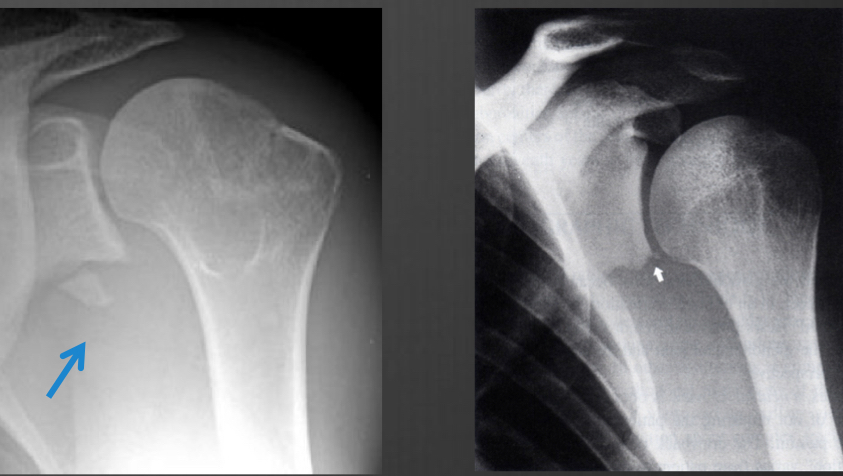

ice cream on a cond lightbulb on a stick is a comon discription of

posterior dislocation in AP view

normal Y

posterior dislocation lateral to the Y

anterior medial to the Y

axial view of posterior humeral head is oppostie to the corocoid process

normal axial

anterior dislocation axial

humeral head overlaps coracoid

this deformity is due to repeated anterior dislocations (and on every baord exam ever per Lauri)

● Hill-Sachs Fx/Deformity

Hill-Sachs Fx/Deformity